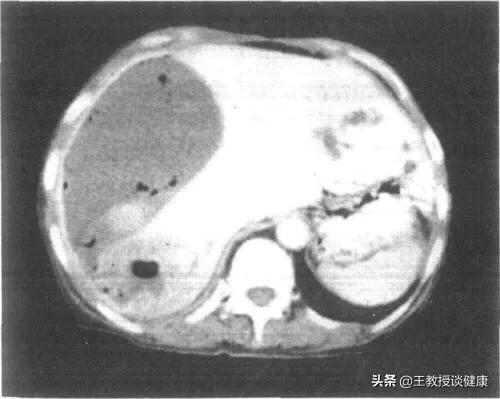

CT检查所见肝右叶肝脓肿影像

CT所见肝右叶肝脓肿明显液化影像